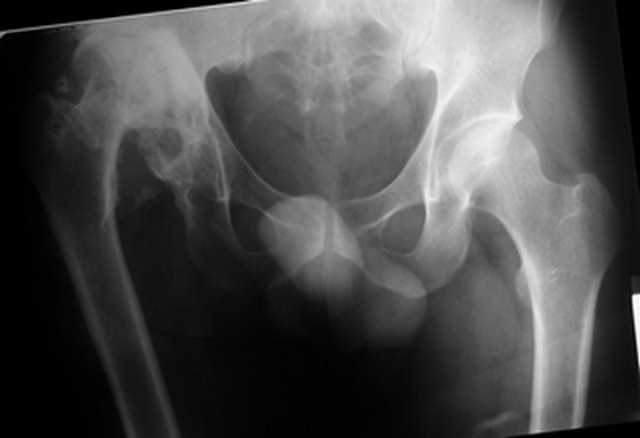

Уважаемые коллеги. Пациент 30 лет 3 года назад в результате травмы получил травматический дефект нижних конечностей до в/3 голеней, был пропущен вывих бедра.

В настоящее время очень неплохо ходит на протезах, движения в неоартрозе близки по объему к здоровой стороне. Основная жалоба - выраженная боль при ходьбе. планируем двухэтапное эндопротезирование - задним доступом мобилизовать проксимальный отдел бедра, резецировать шейку, аппаратом низвести бедро(головку оставить там где она есть, так как больших дефектов не видно(может пригодится в последующем?)). Вторым этапом бесцементное эндопротезирование. Насколько такой вариант реалистичен? Доступ для второго этапа? Может быть другие варианты?С уважением, Максим

На последнем срезе КТ задний край практически отсутсвует по сравнения со здоровой стороной. Разумеется, что это плоскостное изображение, но головка вывихнулась не только в плоскостную щель захваченную на КТ. Если вы считаете, что удастся установить туда чашку даже низкопрофильную, остается пожелать вам успехов. Но перед этим можно смоделировать установку чашки на скиаграммах КТ.

За пожелание успехов - спасибо, думаю это пригодится, не очень понял про плоскостную щель, специально предоставил срезы на уровне свода - он цел, дефект заднего края ниже, за счет заглубления он будет еще меньше, по данным 3d - должно получиться.

Решение по ВВ придется принимать по месту.... Сумеете "подрыться" и получить хорошее покрытие чашки (+2 винта об-но) - хорошо, если нет -

костная аутопластика из головки.